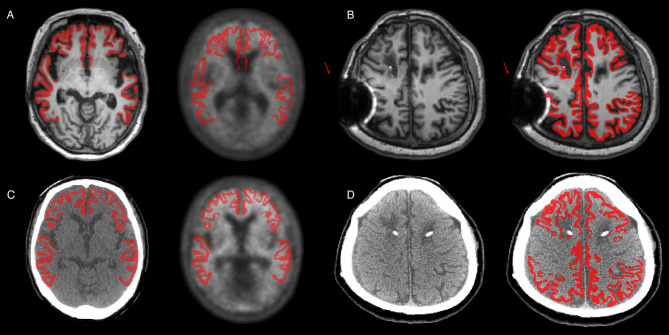

背景:淀粉样蛋白PET/CT对于量化阿尔茨海默病(AD)中淀粉样蛋白- β (Aβ)沉积至关重要,Centiloid (CL)量表标准化了跨成像中心的测量。然而,基于mri的CL管道面临着挑战:高成本、禁忌症和患者负担。为了解决这些挑战,我们开发了一种基于深度学习的CT分割管道,使用PET/CT扫描的CT图像校准到标准CL尺度,并评估其相对于标准管道的性能。方法:共有306名参与者(23名年轻对照[YCs]和283名患者)接受了18次F-florbetaben (FBB) PET/CT和MRI检查。经目测,a β阳性207例,a β阴性76例。PET图像使用CT包裹管道处理,并与FreeSurfer (FS)和标准管道进行比较。通过回归分析评估一致性。使用效应大小、方差和ROC分析来比较管道,并确定相对于视觉Aβ评估的最佳CL阈值。结果:CT分片与FS一致性高,定量CL可靠(R²= 0.99)。这两个管道在YCs和ADCI之间显示出相似的差异和效应大小。ROC分析证实了相当的准确性和相似的CL阈值,支持CT分割作为可行的无mri替代方法。结论:我们的研究结果表明,CT包裹管道在CL量化方面达到了与FS相似的准确度水平,证明了其作为无mri替代方案的可靠性。在PET/CT中,CT和PET在同一时间段内在共用床和头枕上依次获得,这有助于保持一致的定位和适当的空间对齐,减少配准误差,支持更可靠和精确的量化。

Background: Amyloid PET/CT is essential for quantifying amyloid-beta (Aβ) deposition in Alzheimer's disease (AD), with the Centiloid (CL) scale standardizing measurements across imaging centers. However, MRI-based CL pipelines face challenges: high cost, contraindications, and patient burden. To address these challenges, we developed a deep learning-based CT parcellation pipeline calibrated to the standard CL scale using CT images from PET/CT scans and evaluated its performance relative to standard pipelines.

Methods: A total of 306 participants (23 young controls [YCs] and 283 patients) underwent 18 F-florbetaben (FBB) PET/CT and MRI. Based on visual assessment, 207 patients were classified as Aβ-positive and 76 as Aβ-negative. PET images were processed using the CT parcellation pipeline and compared to FreeSurfer (FS) and standard pipelines. Agreement was assessed via regression analyses. Effect size, variance, and ROC analyses were used to compare pipelines and determine the optimal CL threshold relative to visual Aβ assessment.

Results: The CT parcellation showed high concordance with the FS and provided reliable CL quantification (R² = 0.99). Both pipelines demonstrated similar variance in YCs and effect sizes between YCs and ADCI. ROC analyses confirmed comparable accuracy and similar CL thresholds, supporting CT parcellation as a viable MRI-free alternative.

Conclusions: Our findings indicate that the CT parcellation pipeline achieves a level of accuracy similar to FS in CL quantification, demonstrating its reliability as an MRI-free alternative. In PET/CT, CT and PET are acquired sequentially within the same session on a shared bed and headrest, which helps maintain consistent positioning and adequate spatial alignment, reducing registration errors and supporting more reliable and precise quantification.